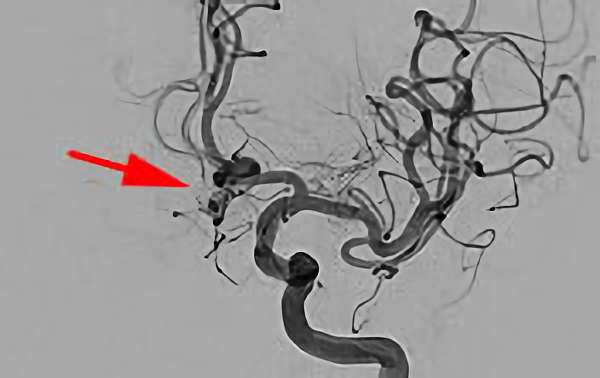

脳動脈瘤(血管内治療)実績一覧 (合計 791 件)

※ 画像をクリックすると拡大表示します。症例No.をクリックすると詳細ページを表示します。